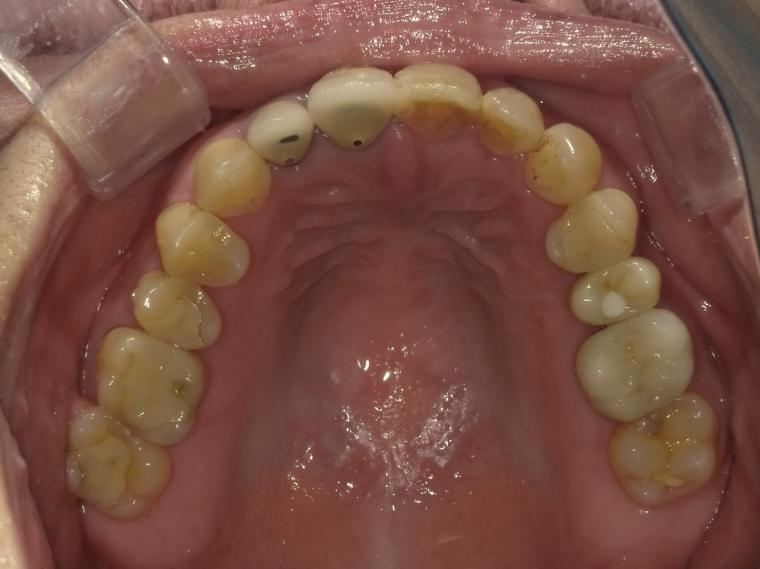

AFTER

58歳女性/上下2本欠損/インプラント埋込手術

左上第二小臼歯が欠損状態で、インプラントのご相談でご来院された患者さんです。

左下第一大臼歯も、根っこの先で炎症が広がっており、抜歯後に左上と一緒にインプラントを埋入しました。

現在も定期検診で拝見させていただいています。